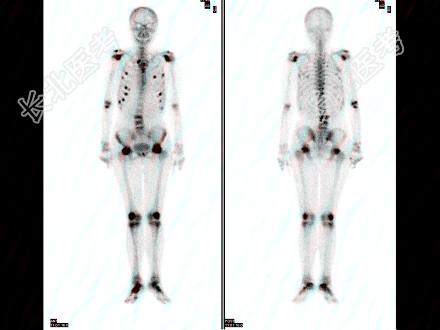

- 多项选择题女性,72岁, 双下肢间歇性钝痛3个月,现行走困难, SCr256μmol/L,HGB68g/L, 骨显像最可能的诊断是 ( )

A、双侧股骨头缺血性坏死

B、多发性骨髓瘤

C、多发的骨转移癌

D、腰椎有病理性压缩

E、肋骨浓聚点全部是骨质破坏